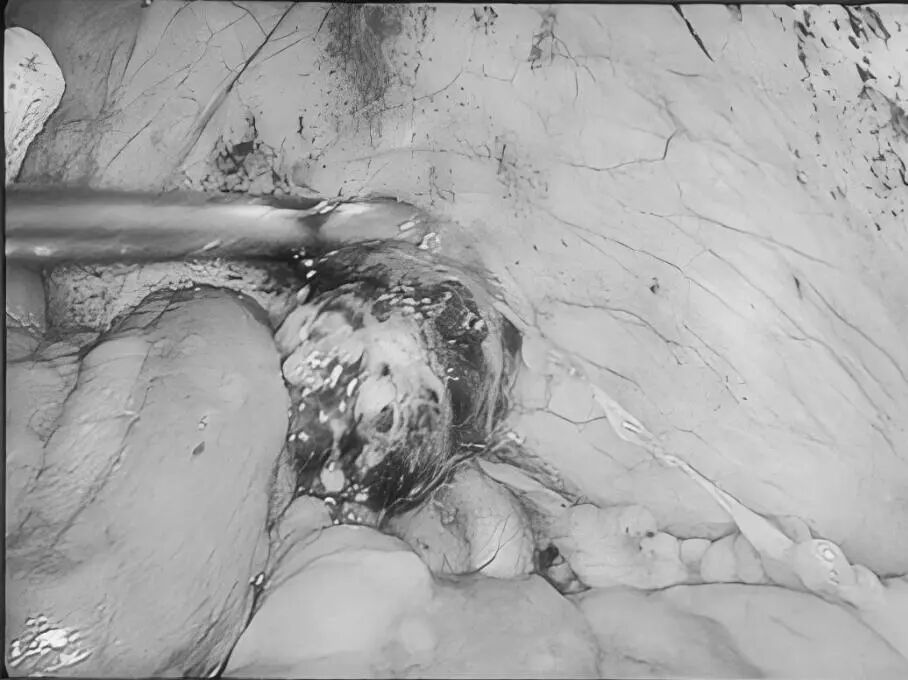

8月27日,贵州航天医院第75次晨读会由我院柔性引进的知名肛肠外科专家高大勇教授作学术交流,他以“肛肠科常见病浅谈”为题,系统讲解了痔疮、肛裂、肛周脓肿等常见肛肠疾病的症状表现、潜在风险及相应治疗方式,为医院带来了前沿医疗理念与技术,有效提升了医务人员对肛肠疾病的早期识别与诊疗水平,也为学科建设、临床诊疗能力的长效提升奠定了坚实基础。 贵州航天医院 普外科专家简介 高大勇 普外科(肛肠外科)学科带头人、名誉主任,主任医师、教授 临床擅长:对中西医结合诊治肛肠学科各种常见病、多发病及疑难杂症等具有丰富的临床经验。 原遵义市第一人民医院(遵义医科大学第三附属医院)、遵义市中医院肛肠科主任。中华中医药学会肛肠分会常委,全国中医肛肠学科名专家,中国健康促进与教育协会肛肠分会常委,中国康复医学会肛肠疾病康复专业委员会常委,中国民间中医医药研究开发协会肛肠分会副秘书长,中国医师协会中西医结合肛肠医师专业委员会常委,国家二级心理咨询师,贵州省第一批中医名医工作指导老师,遵义市名中医,遵义市肛肠学会会长,遵义市肛肠质控中心名誉主任,遵义市中西医结合学会名誉会长,遵义市健康科普专家,原贵州省中西医结合学会肛肠分会副主任委员、贵州省中医肛肠质控中心副主任、遵义市医学会医疗鉴定委员会专家、遵义市卫生系列高评委。发表论文30余篇,主编和参编医学著作5本,主持省级科研课题2项、市级科研课题2项、院级科研课题1项。 梁   跃 中共党员,普外科党支部书记、主任,主任医师 临床擅长:对普外科各类肿瘤手术具有丰富的临床经验。 毕业于遵义医学院,遵义市医学会小儿外科学分会常务委员,遵义市肛肠协会理事,遵义市医学会核医学分会(第二届)委员会委员;荣获第三期“黔医人才计划”优秀学员称号;主持市级课题1项,完成省级课题1项,在国内各类刊物上发表论文10余篇。 钱科洪 民盟盟员,普外科副主任医师 临床擅长:从事普外科临床工作30余年,对各类普外科疾病的诊治、乳腺、甲状腺、胃十二指肠、结直肠等疾病及疑难杂症具有丰富的临床经验。 毕业于遵义医学院临床医疗系,2009年前往中山大学附属第一医院微创外科进修学习,在国内各专业期刊发表论文数篇。 贵州航天医院 普外科简介 基本情况 贵州航天医院普外科成立于1968年,前身属于航天部O61基地3417医院外一科,1998年3417医院、3427医院合并后更名为普外科,下设胃肠外科、肛肠外科2个亚专业科室,拥有在全市较为先进的专科设备和技术,是中国疝病专科联盟单位,贵州医科大学附属医院胃肠外科专科联盟单位。开放床位40张,配备医护人员21人。 专科特色技术 普外科致力于胃肠及肛肠疾病的外科临床诊治及科研,以腹腔镜微创外科技术为本,形成以快速康复治疗胃肿瘤、结直肠肿瘤、小肠肿瘤、直肠脱垂、肥胖病、急腹症、各类疝、痔、瘘等专科特色,同时注重胃肠疾病尤其是结直肠恶性肿瘤的基础研究和临床转化研究,总体诊断和治疗水平在区域同级医院居于领先水平。 开展手术:腹腔镜下胃癌根治术,腹腔镜下袖状胃切除术,腹腔镜下胃肠道间质瘤切除术,腹腔镜下结、直肠癌根治术,胃癌、结直肠癌的精准治疗,腹腔镜下小儿疝气、成人疝修补术,腹腔镜下阑尾手术,内痔的硬化注射治疗及痔疮的微创治疗:ATH、PPH、TST,直肠脱垂的各种手术治疗,难治性伤口VSD技术,鼻胃肠管、肠梗阻导管置入术,肛肠术后间歇性导尿技术,并引进了中医适宜技术,也为各种化疗患者提供输液港安装,提高患者就医体验。 腹腔镜下腹股沟疝 无张力修补术 腹股沟疝里金斯坦(Lichtenstein)手术 PPH微创术治疗环状混合痔 黏连性或炎性肠梗阻-肠梗阻导管 腹腔镜袖状胃切除 腹腔镜阑尾切除术 腹腔镜阑尾肿瘤切除术 腹腔镜下结肠癌根治术 科室诊疗范围 胃肿瘤、结直肠肿瘤、小肠肿瘤、肥胖症、各类急腹症、腹部外伤、腹壁疝、便秘、直肠脱垂、痔疮、肛瘘、肛裂等胃肠、肛肠外科疾病。 end